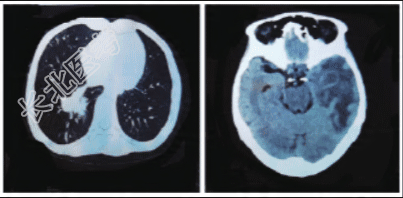

患者,女,63岁,农民。因“咳嗽、咳痰4个月,发现肺部、颅内占位1月余”入院。患者被家人发现不能言语,答非所问,于当地医院就诊。头颅+胸部CT:左侧额叶转移瘤伴水肿可能大,右肺下叶阻塞性肺炎,左肺下叶占位;两肺多发陈旧灶。PET-CT示左侧颞叶不规则环形稍高密度影,SUV最大值11.9,右肺下叶见3.9cm×3.0cm分叶状团块影,SUV最大值9.3,考虑右下肺癌伴右肺转移、肺下叶阻塞性炎症,右肺门淋巴结转移,左颞叶脑转移。脱水改善脑水肿治疗后,失语情况明显改善。

入院后癫痫发作1次。查体:体温38.7℃,血压140/80mmHg(1mmHg=0.133kPa),神志清,精神差,答非所问,失语,体型消瘦(身高1.5m,体重35kg)。四肢肌力Ⅳ级,肌张力正常,余未见明显异常。辅助检查:血常规示白细胞计数7.83×10⁹/L,中性粒细胞绝对值6.8×10⁹/L,血红蛋白96g/L,血小板计数153×10⁹/L,C反应蛋白(CRP)7.6mg/L;肿瘤标志物:CA125157.9U/ml,CA15330.65U/ml,神经元特异性烯醇化酶23.96ng/ml;ANA抗体谱:抗核抗体、SS-A/Ro52阳性,胞浆颗粒型阳性(1∶320),抗环瓜氨酸肽抗体27.9RU/ml。血G试验、GM试验、乙肝五项、丙肝抗体、梅毒抗体、HIV均阴性,免疫球蛋白、补体、淋巴细胞亚群均正常范围。眼科评估未见干眼。腮腺显像示双层腮腺摄取及分泌功能减退。痰液抗酸染色、X-pert阴性。头颅强化MRI示圆形或类圆形的囊状颅内占位,囊壁较薄,大小不等(图2)。腰穿CSF检查:压力90mmH₂O(1mmH₂O=0.0098kPa),淡黄色澄清。CSF培养、结核X-pert、隐球菌荚膜抗原染色阴性;淋巴细胞增生活化伴中性粒细胞增多,部分呈凋亡趋势;可见少量单核巨噬细胞,未见恶性肿瘤细胞证据;潘氏试验(+++),有核细胞3×10⁶/L,红细胞50×10⁶/L;蛋白3.37g/L,葡萄糖2.08mmol/L,氯化物102mmol/L,乳酸3.6mmol/L。CSF二代测序示为脓肿诺卡菌(序列数3995,置信度高)。诊断:诺卡菌性脑脓肿。